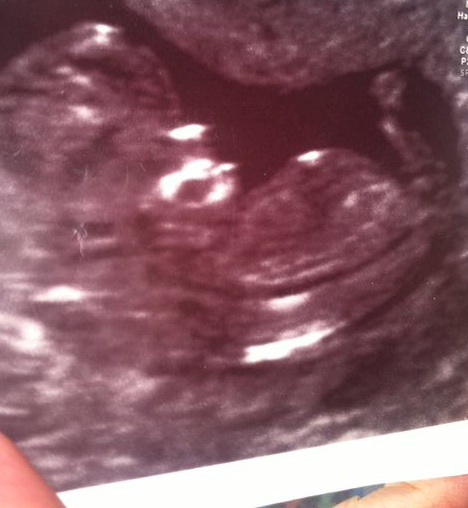

Hi, I have already posted this scan picture. But I am curious to know what part is the nub?

12.2 weeks. What part is the nub? Thank you x

It's the straight flat white line at the end of the torso...long and thin like a needle. Baby girl!

white line at the end of the body. looks girly!